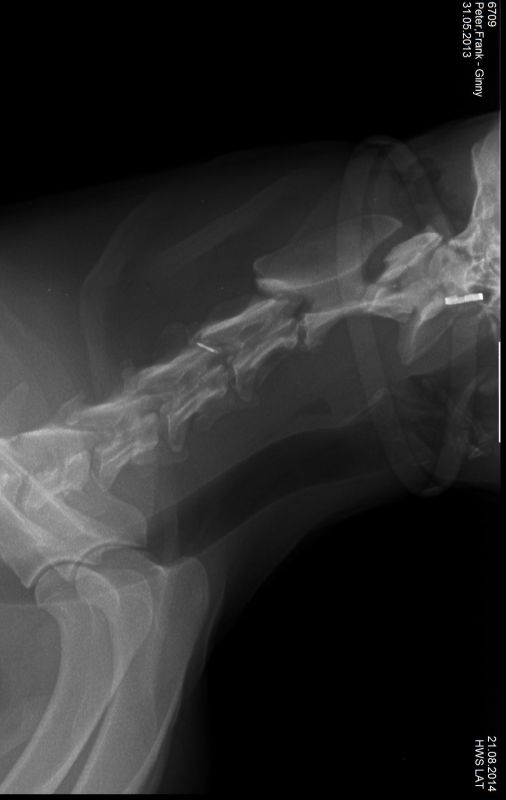

21.08.2014 - Ginny HD-und ED geröntgt - 15 Monate alt

24.08.2014 - Ginny - 15 Monate alt